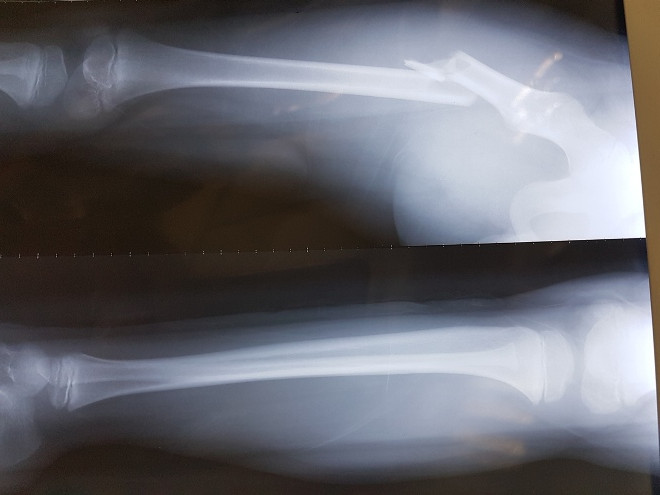

Ảnh chụp X.Quang của bệnh viện Việt Đức cho thấy học sinh bị gãy đôi xương đùi